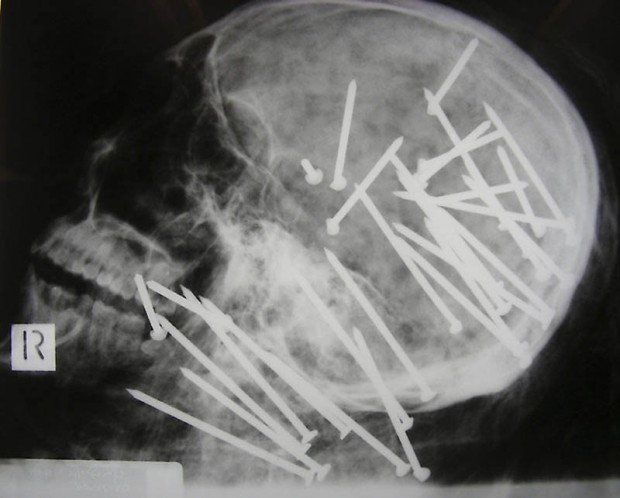

1. Череп китайца, которому в голову выстрелили пневматическим молотком.